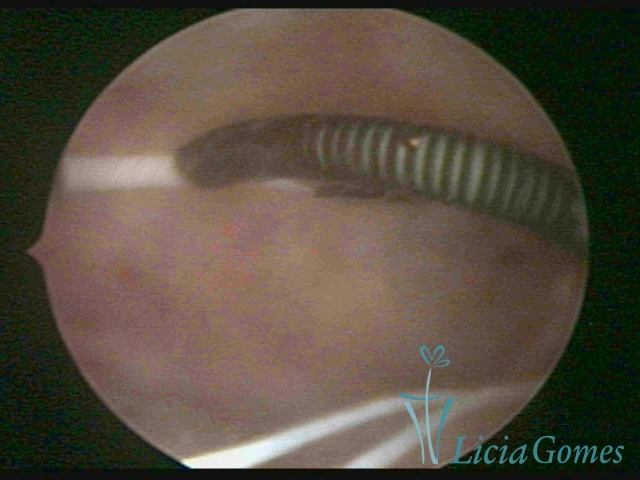

Canal cervical com fio do DIU